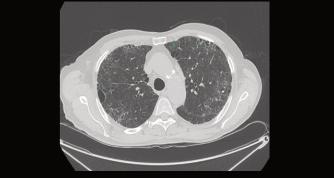

LaTomografíaComputadapulmonaryTomo‐grafíapulmonardealtaresolución(TACAR) permiteestudiarloscambiosmorfológicos pulmonaresenlaCOVID-19desdeeliniciode

lossíntomashastalarecuperaciónfinal. Permiteladetecciónprecozdefibrosispulmo‐nar,valorarsudistribuciónysuextensión,ya queeslasecuelacrónicamástemida(Fig.1). Laimportanciadeladetecciónoportunade estasalteracionespulmonarespos-COVID-19 radicaenqueunmanejooportunoconreha‐bilitaciónpulmonarpuedecontribuiradismi‐nuirlossíntomasymejorarlacalidaddevida delospacientes.